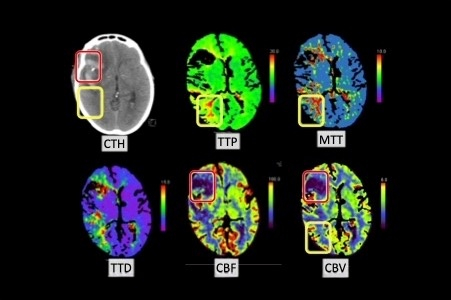

Figure 1. Multi-modal CT perfusion (CTP) imaging; The red boxes delineate areas of severe hypoperfusion following a subarachnoid hemorrhage characterized by reduced CBF and potentially CBV with prolonged TTP/MTT. The yellow boxes highlight regions with less severe perfusion deficits, potentially representing areas at risk for DCI. These maps are crucial for identifying and monitoring DCI.

CBF, cerebral blood flow; CBV, cerebral blood volume; CTH, computed tomography head; MTT, mean transit time; TTD, time to dispersion; TTP, time to peak.

These advanced computed tomography (CT) techniques provide a more direct and comprehensive assessment. CT angiography (CTA) offers rapid, high-resolution anatomical visualization of the cerebral vasculature, demonstrating high sensitivity (80%) and specificity (93%) for detecting proximal vasospasm. CT perfusion (CTP) moves beyond anatomy to physiology by tracking an intravenous contrast bolus to generate quantitative maps of key perfusion parameters, including CBF, cerebral blood volume (CBV), and mean transit time (MTT). This allows clinicians to visualize areas of hypoperfusion directly. A CBF value below a critical threshold of 25 mL/100g/min is a strong indicator of tissue at high risk for infarction and clinically relevant DCI. The ability of CTP to distinguish true hypoperfusion from the high-velocity state sometimes seen in TCD represents a significant diagnostic advantage.